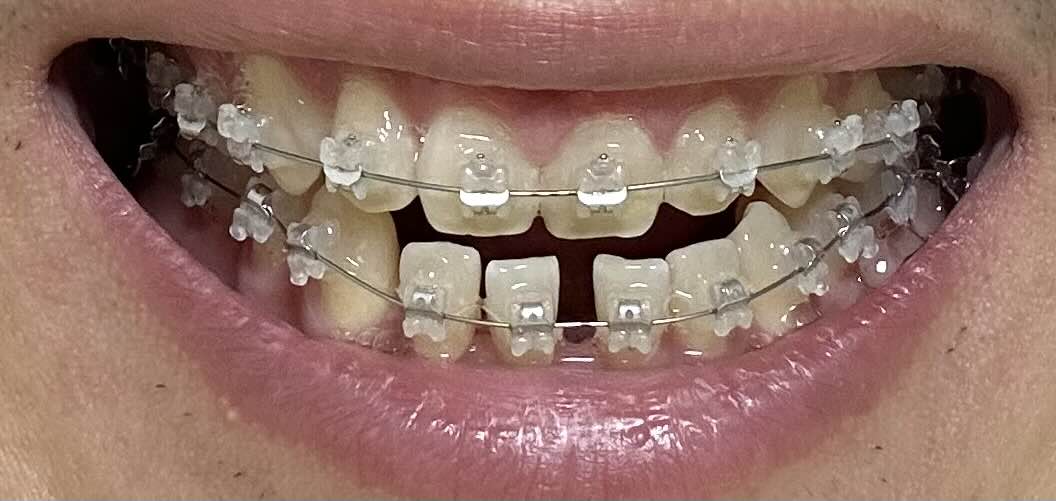

9월2일 교정 1일차

사실 교정기를 장착했을뿐이지 교정이 크게 되거나 한 모습은 없습니다. 당연히 하루 밖에 안됐으니까 그렇겠지만요. 이때만해도 교정이 어떻게 되지? 라고 생각했을때인데요.

10월1일 교정 한달 차

교정 한달이 지난 모습을 보니까 확실히 앞니의 모습이 많이 괜찮아졌습니다. 처음에는 정말 아팠는데 말이죠. 벌어진 부분이 많이 사라졌고, 돌아갔던 부분도 어느정도 일자로 반듯해지고 있는게 보이네요. 정말 신기하죠? 우선 앞니부터 돌리고 안쪽으로 밀어넣을 예정이라고 하니까요. 1년 6개월 정도 예상을 하고 있는데 벌써 이렇게 반듯해진 모습이 기대가 됩니다.